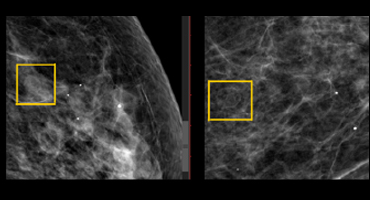

QUISTE OLEOSO

Mamografía